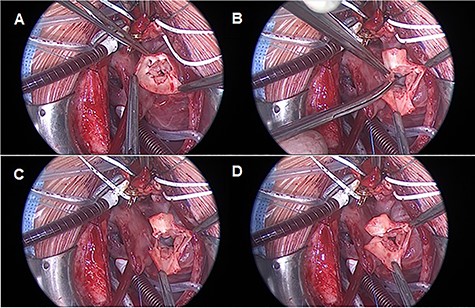

Median sternotomy is performed, and anatomy is confirmed. The pulmonary arteries are mobilized as much as possible. To achieve cardiopulmonary bypass (CPB), the arterial cannula is inserted in the aortic arch, venous cannulas in the superior and inferior venae cavae. After starting CPB and induction of ventricular fibrillation, the right atrium is opened and cold cardioplegic solution is infused into the coronary sinus under pressure control (Buckberg’s solution, 30-ml/kg/body weight induction, pressure < 30 mmHg). This is followed by the transverse opening of the trunk vessel with a distance to the branches of the coronary vessels. Inspection of the truncus valve, in our case it was severely incompetent in the pre-operative transesophageal echocardiography, showed four cusps and asymmetrical sinuses. Three sinuses and the associated valve leaflets are roughly the same size; the fourth sinus and corresponding valve leaflet are much smaller and, most importantly, have no relation to a coronary ostium. The hypoplastic valve leaflet is resected together with the sinus of the trunk vessel up to the commissures of the adjacent valve cusps (Fig. 2).

TV reconstruction. (A) Leaflet identification. (B and C) Leaflet resection. (D) Local annuloplasty and aortic valve suture.

These adjacent commissures are then sutured longitudinally starting from the valvular ring with a continuous 7–0 polypropylene suture.

Care must be taken that through the resection of the cusp and the corresponding sinus, no valvular stenosis is caused. In our case, the ring diameter was −1 Z score after reconstruction. The further course of the operation is carried out as standard with resection of the pulmonary vessels from the trunk and connection to the RVOT by means of an REV maneuver.